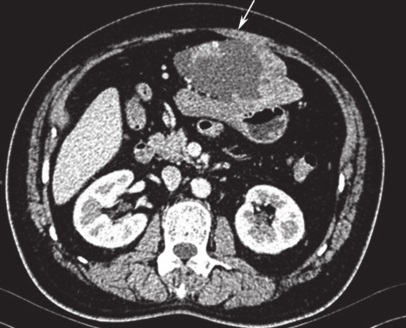

1小时条评论胃肠间质瘤(gastrointestinalnbsp;stromalnbsp;tumor,GIST)大体病理特点多为规则、质软的实质性肿块。虽然有部分GIST呈囊性变,但极少GIST发现时即为显著囊性变,实性部分仅占极低比例。这类呈显著囊性变的GIS...